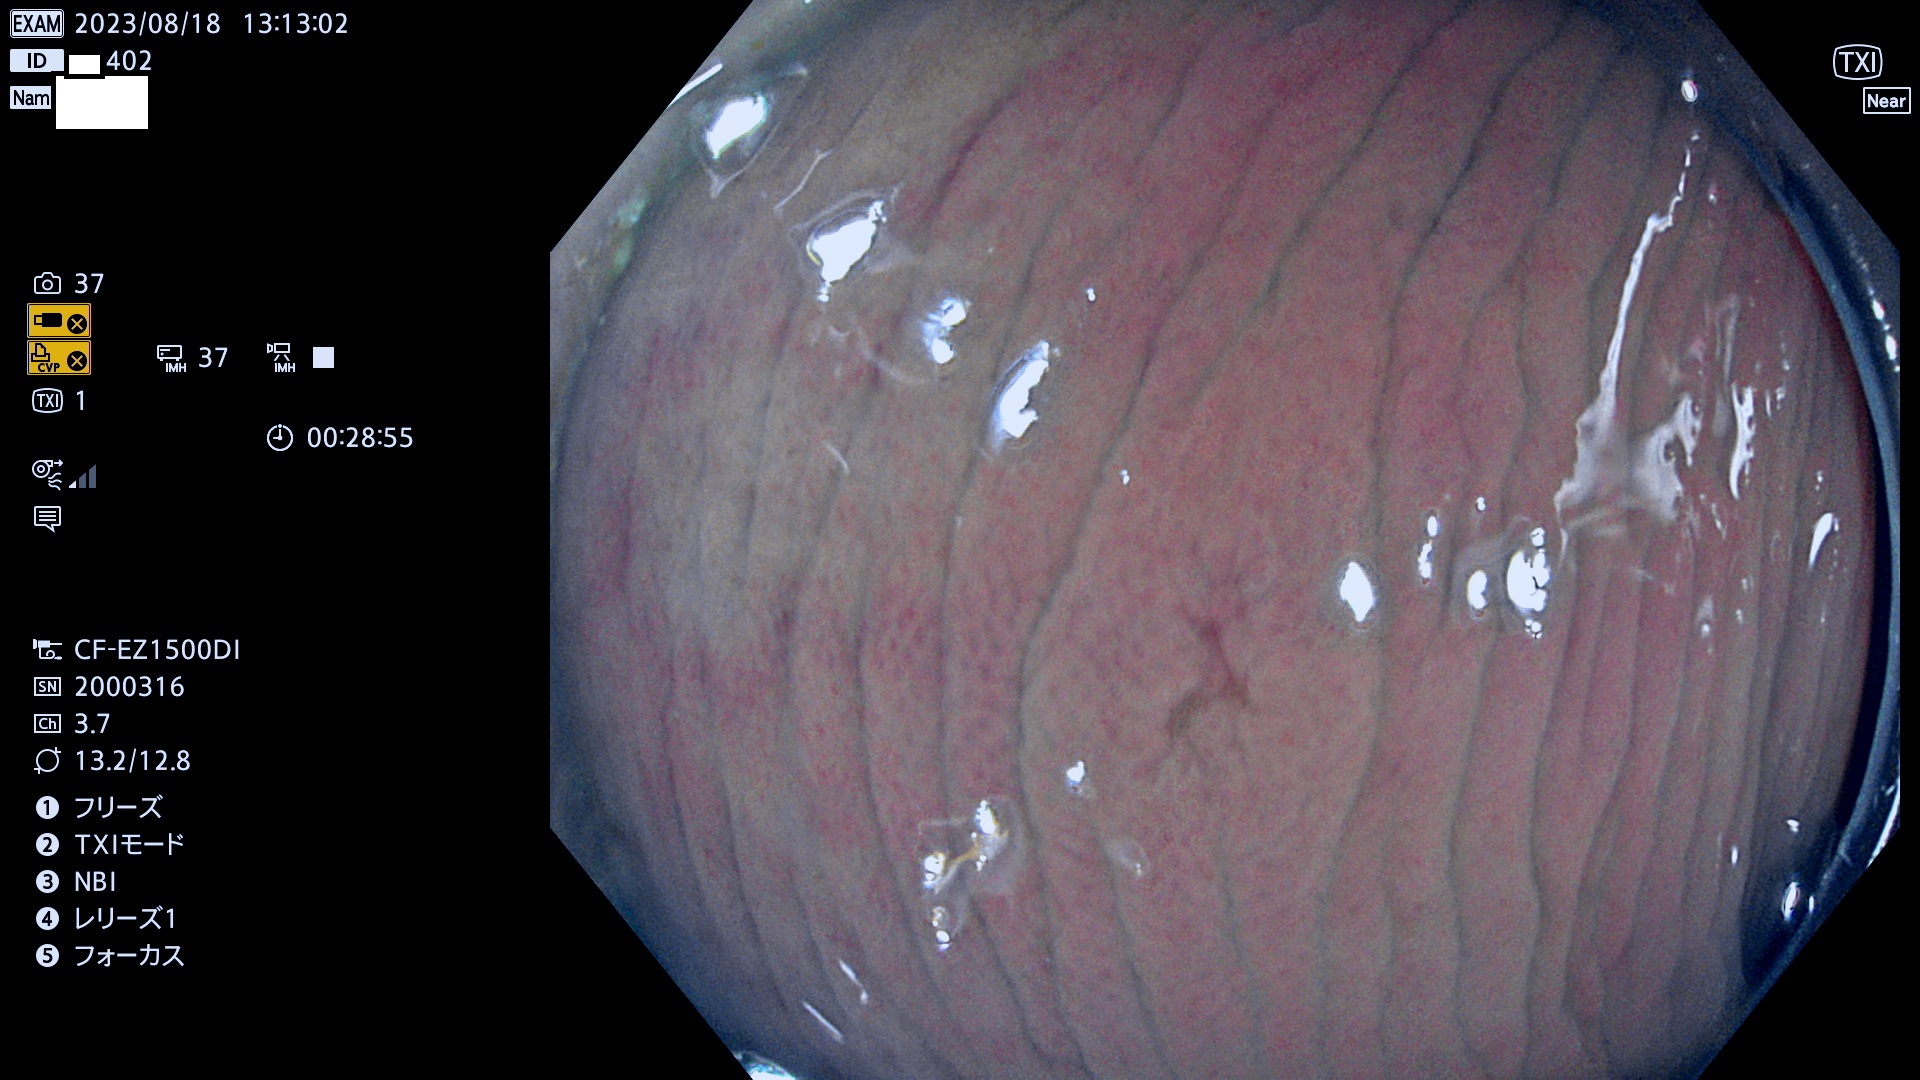

表面型腺腫(Flat Adenoma)の中で、完全に平坦な物をUb、陥凹している物をUcと呼びます。平坦隆起型(Ua)よりも、発見が難しく危険な病変です。このタイプは「内視鏡後・大腸癌の重要犯人」であり、この発見率は「腺腫発見率」よりも、重要な意味があります。

毎週の検査(木・金・土・日)に発見されたUb、Uc型・腺腫を、その週の日曜の夜にUPし1週間、提示します。

抽出の対象期間 2023年8月17日(木)〜8月20(日)の4日間(48件の検査)11件